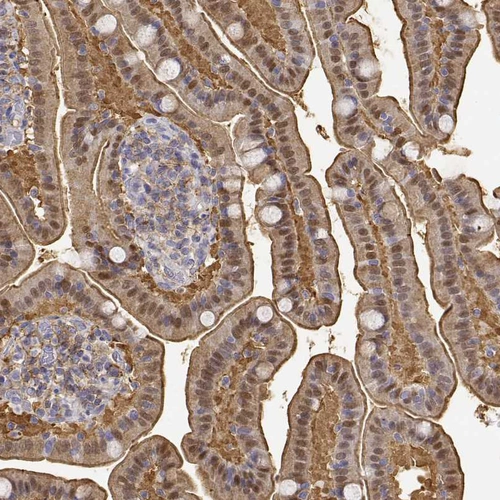

Immunohistochemistry analysis in human duodenum and testis tissues using HPA023884 antibody. Corresponding ADA RNA-seq data are presented for the same tissues.